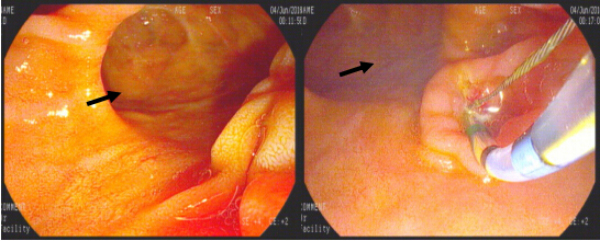

2016年7月13日,由赵刚主治医师操作,在左爱丽护士长、李婵护士、杨龙宝博士的协助下,在密切监护患者生命体征的同时对其实施ERCP手术。术中可见患者十二指肠降部有多发巨大憩室,十二指肠乳头位于其中一憩室内,属于憩室内乳头的情况,操作稍有不慎即可能引起十二指肠穿孔。一次性顺利插管至胆总管并造影,确认了胆管中结石的大小约1.2cmx1.4cm,位于肝总管处(结石可能由于插管及造影发生了位移),同时也发现由于憩室的压迫,患者胆管走形异常扭曲。我们对该患者的十二指肠乳头进行了小切开并以1.2cm胆管扩张球囊进行扩张,后以取石球囊顺利自胆管中取出巨大成型结石一枚,再次造影胆管内未见残存结石,遂置入鼻胆管,整个操作过程用时仅30分钟。患者术后第2天即恢复正常饮食,腹痛症状基本消失,目前已经顺利出院。

十二指肠乳头位于一巨大憩室内(黑箭头所示为憩室)